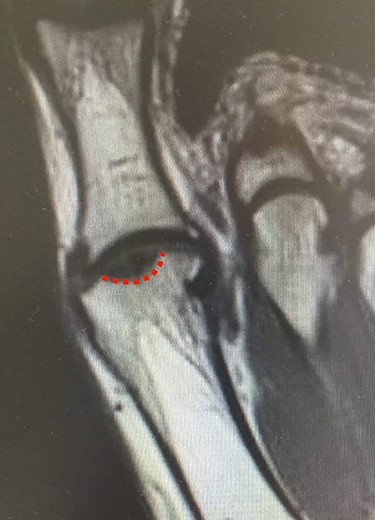

MRI (sagittal view) of the left foot. The red dots show a deep MH defect involving the subchondral bone, a typical finding of OD.

Standing anteroposterior (AP), oblique and lateral radiographs of the affected foot were taken. On the AP and oblique views, an OD lesion of the 1st MH was visible (lytic lesion of the subchondral bone and subchondral sclerosis formation) with a lateral-forming osteophyte (Fig. 1A and B). Magnetic resonance imaging (MRI) of the left foot clearly shows the osteochondral defect of the 1st MH (Figs 2 and 3).